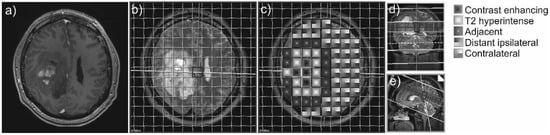

31P-MRS was performed on a 3T whole-body system (Verio, Siemens Medical AG, Erlangen, Germany) with a double-tuned 1H/31P volume head coil (Rapid Biomedical, Würzburg, Germany). For planning of the 31P-MRS, a sagittal-oriented T2-weighted 3D sequence (space) with isotropic resolution and a voxel size of 1.2 × 1.2 × 1.2 mm³ (repetition time (TR) = 3000 ms, echo time (TE) = 412.0 ms, acquisition time (TA) = 2:50) was acquired. The 3D MRS block was acquired, covering the entire cerebrum of the patients. As much volume of the brain as possible was covered by using the following planning protocol: aligning the coronal inclination on the dorsal line of the brain stem and axial arrangement in the subcranial layers (Figure 1). Inclusion of cavities and skull was avoided as fat, bone, and boundary layers would be intruding the 31P spectra.

Figure 1.

Example of a contrast-enhancing GBM (a) and the 31P-MRS measure grid coregistered to the axial T2-weighted sequence of a patient with GBM (b). The different areas of interest are coded with different patterns (c). On the right side, coronal (d) and sagittal (e) slices display the position of the voxel slice within the brain.

The following brain areas were analyzed with one or more 31P-MRS voxels in each patient: CE tumor areas, not CE T2-hyperintense areas, normal-appearing brain areas adjacent to the T2-hyperintense areas, normal-appearing brain areas more distant on the ipsilateral hemisphere, and normal-appearing brain tissue areas on the contralateral hemisphere (Figure 1).